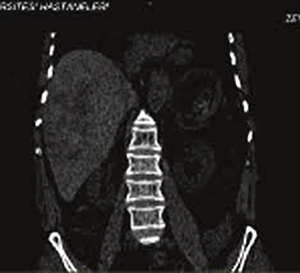

Lee (2006) ở Hàn Quốc báo cáo về ca bệnh sán Fasciola sp. nữ 46 tuổi, lạc chỗ trong tụyhiếm thấy, nếu sán xâm nhập vào nhu mô thì nghiên cứu lâm sàng có những hạn chế trong việc phát hiện sán và khi đó phẩu thuật là cần thiết để xác định. Ca bệnh này được chẩn đoán thông qua bằng chứng gián tiếp. Ca bệnh này nhập viện với bệnh cảnh đau hạ sườn (T), có dùng praziquantel để điều trị sán từ một chẩn đoán của bệnh viện tuyến trước, sau đó không khỏi mà còn đau bụng tăng hơn. Xét nghiệm máu ngoại vi cho thấy bạch cầu ái toan tăng, tăng amylase và lipase huyết thanh. Chụp CT-scanner ổ bụng thấy hình ảnh đa ổ giảm âm kèm theo tạo khối, hình thành các nốt không đồng đều trong đoạn cắt ra vùng thùy bên (T) của gan và kích thước đường kính 2-3 cm, tổn thương giảm âm trong vùng eo và thân tụy. Kháng thể IgG chống lại F. hepatica dương tính. Điều trị bằng thuốc bithionol và các triệu chứng cải thiện, trị số bạch cầu ái toan trở về bình thường. Chụp CT-scanner cho hình ảnh gan và tụy trở về bình thường ở tuần thứ 10 và huyết thanh kháng F. hepatica âm tính sau đó 5 tháng.